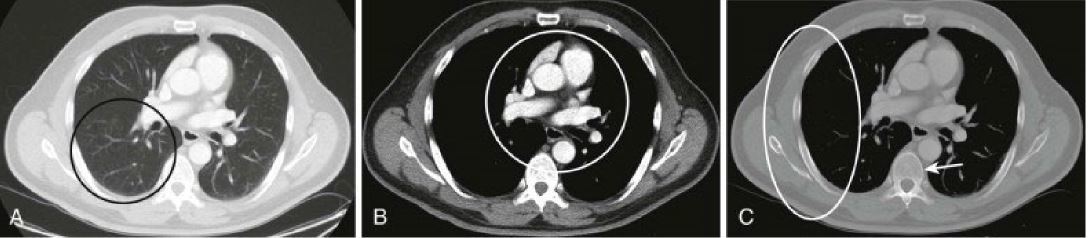

-imaging modality -orientation -window -body part

-IV contrast enhanced CT -axial - chest - lung, soft tissue, bone

Q

-imaging modality -orientation -window -body part -which image has contrast? -what is abnormality?

A

-CT -axial -soft tissue -abdomen -right image; -liver tumors

-imaging modality -orientation -window -body part -iv contrast -abnormality

-CT -axial -soft tissue -chest -yes -large l perihilar lung mass invading left pulmonary artery

-CT -axial -lung -chest -yes -left lung carcinoma